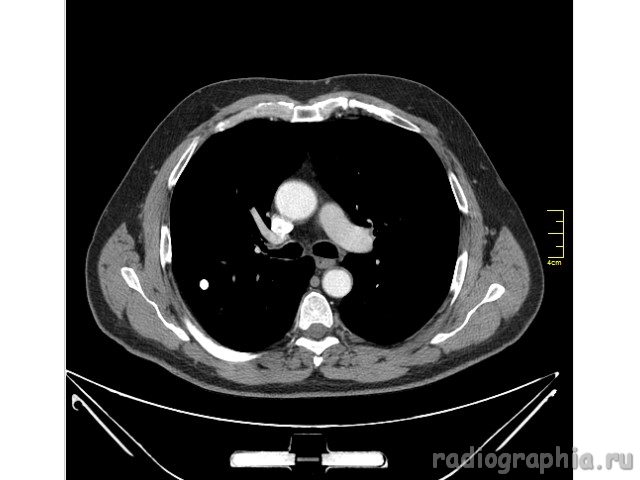

Одиночный узел правого лёгкого.

На рутинном снимке ОГК, был выявлен одиночный узел; по протоколу выполнили КТ. Какое было бы ваше заключение; и как бы Вы поступили если у вас нет возможности выполнять КТ?

Routine Chest X-Ray. SPN (solitary pulmonary nodule-red arrow)